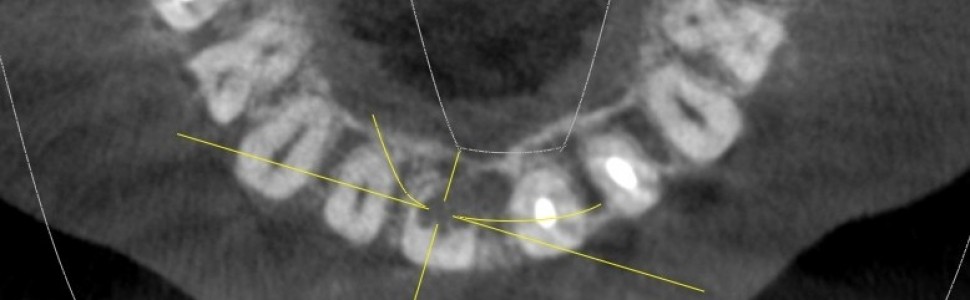

Resorpcja wewnętrzna zęba siecznego przyśrodkowego w dwóch odsłonach. Leczenie zachowawcze oraz implantoprotetyczne w odcinku przednim

Resorption of the internal central incisor in two cases. Conservative and implantoprosthetic treatment in the anterior region